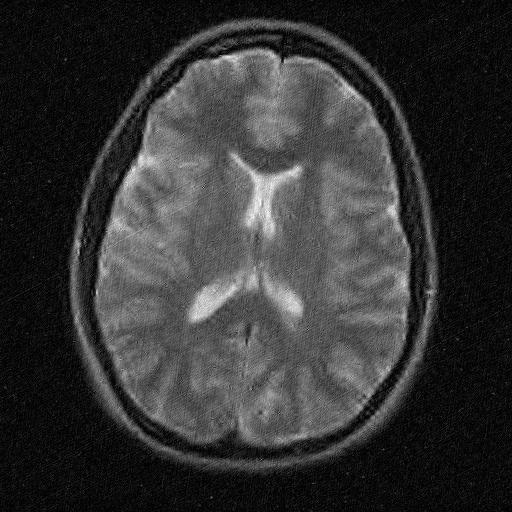

• [39] T. Zhang. Sparse recovery with orthogonal matching pursuit under rip. Information Theory, IEEE Transactions on, 57(9):6215–6221, 2011.